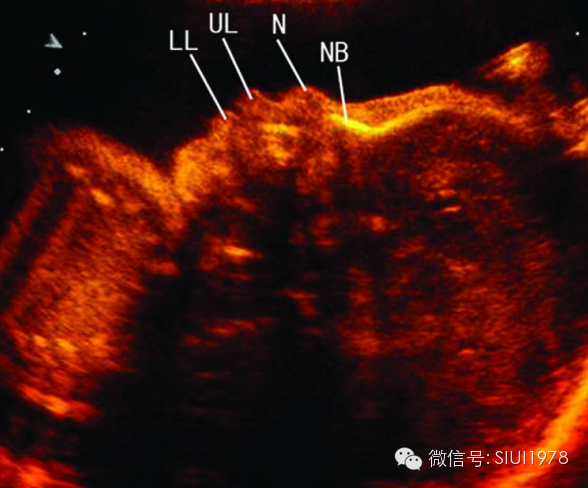

(三)正中矢状切面

1.扫查方法:胎儿仰卧位,探头置于胎儿面部正前方,声束平面通过胎儿鼻尖和额部作正矢状切面扫查,即可获此切面。

2.判断标准:下颌骨仅为圆点状高回声,鼻尖显示的同时只显示鼻柱,而不能显示鼻孔,同时显示额部而非眼眶回声。

3.主要观察的解剖结构及内容:前额、 鼻根、 鼻尖、 鼻柱、 上唇、 下唇、下颌及其深部的骨性结构如额骨、 鼻骨、上颌骨牙槽突、 下颌骨牙槽突,还可观察到口腔及舌,下巴则表现为有一定曲度的“S” 形。声束平面略向左或右平行移动,可显示出鼻孔、 眼球等结构。

4.临床意义:该切面是观察胎儿面部轮廓的良好切面,某些特征在诊断与鉴别诊断颜面部异常时有非常重要的意义,尤其是有面部中线异常的畸形,该切面诊断意义较大,如前额后缩(小头畸形)、前额前凸(颅内肿瘤及额部脑膨出)、无鼻或鼻发育不良、喙鼻、鼻骨发育不良或缺失、 、 双侧唇腭裂所致上颌骨前突、口腔畸胎瘤、舌血管瘤、小下颌、无下颌并耳畸形等。